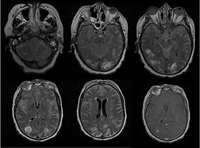

Séries de imagens de ressonância nuclear magnética (RNM) do cérebro de um paciente com encefalomielite disseminada aguda: lesões assimétricas "felpudas" sobre os cornos ventriculares bilaterais e tálamos

Do acervo pessoal de Catalina C. Ionita, MD; usado com permissão

Veja esta imagem em contexto nas seguintes seções: